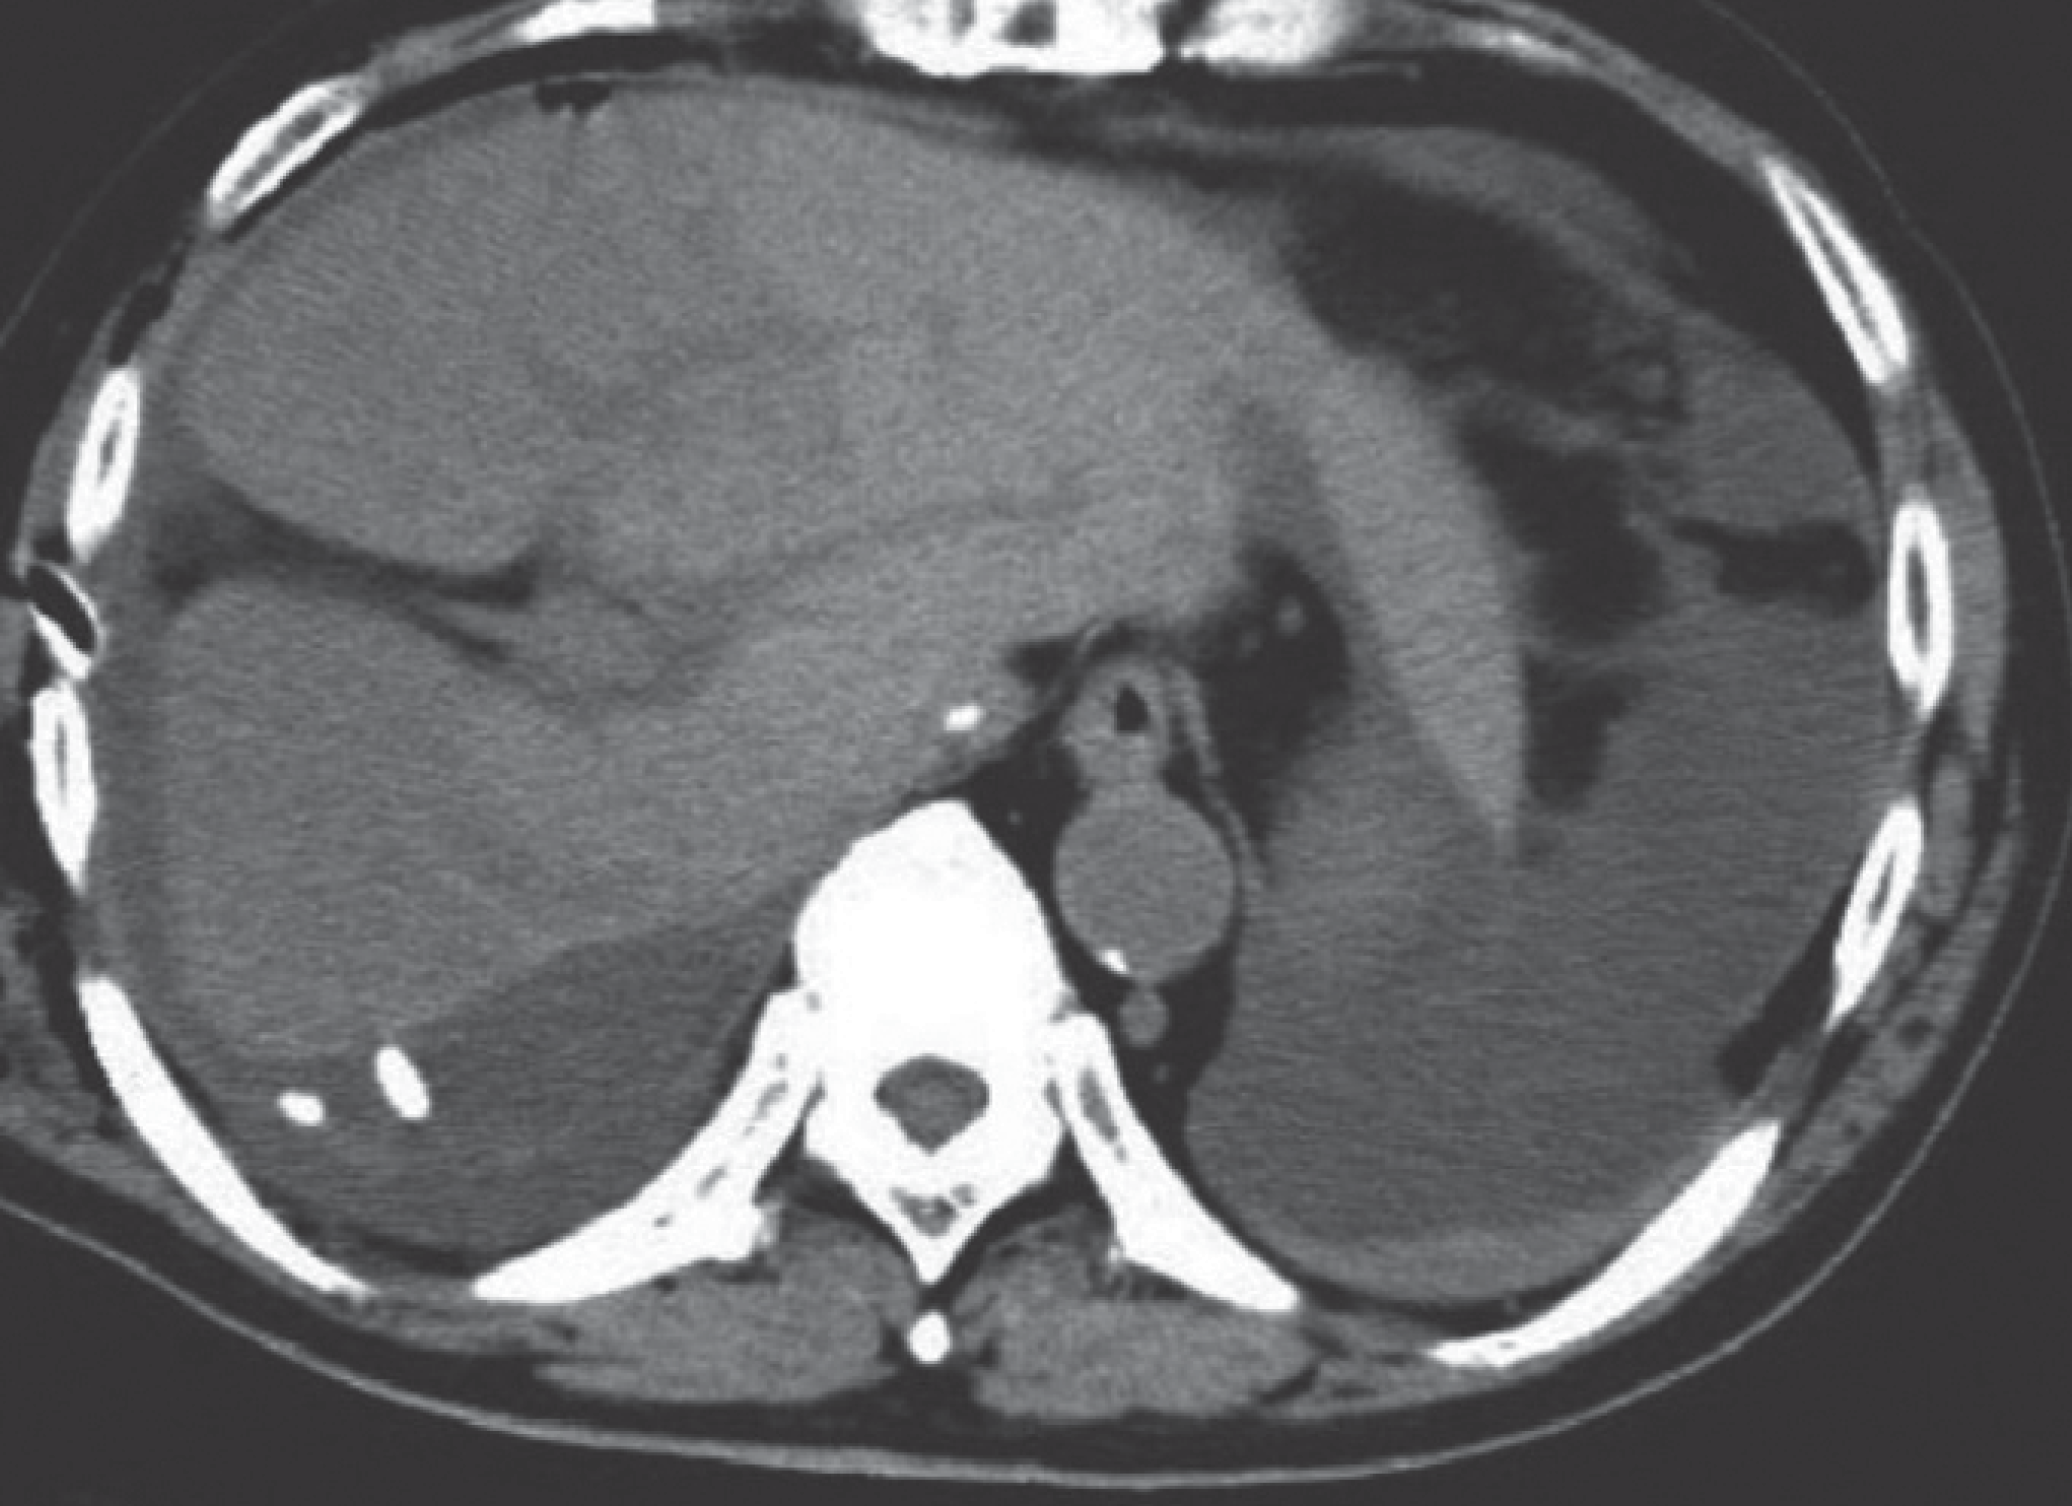

Management of Cystic Neoplasms of the Pancreas

- Updated guidelines for pancreatic cyst management have recently been released, including the 2018 European Consensus Guidelines, the 2017 American College of Radiology Guidance, and the 2016 Revisions to the International Consensus Guidelines.

- Epithelial histologic subtypes of intraductal papillary mucinous neoplasms have been shown to have important implications for prognosis.

- Pancreatic cyst fluid analysis for DNA biomarkers has shown promise for cyst diagnosis and detection of malignancy in the PANDA clinical trial and other studies although utility in clinical practice has not been demonstrated.

- A multidisciplinary team at Johns Hopkins Hospital published details of their multidisciplinary pancreatic cyst clinic outcomes, the first of its kind reported in the literature.